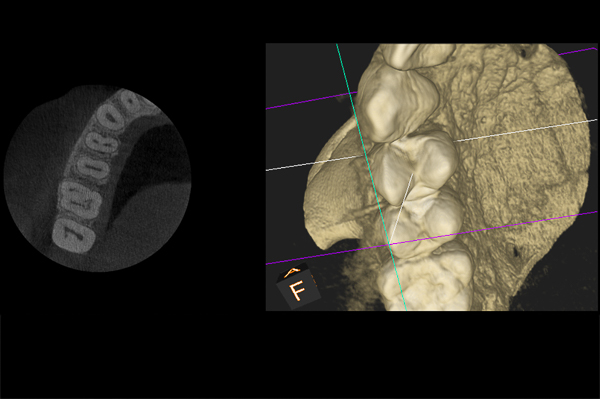

Il caso presenta la riabilitazione di un premolare superiore interessato dal fallimento di un trattamento endodontico in una paziente donna di 37 anni, non fumatrice e con una buona igiene.

A seguito dell'analisi radiografica viene pianificata l'estrazione atraumatica del premolare con l'inserimento contestuale di un impianto Shelta. La riabilitazione immediata viene eseguita con un pilastro XA per protesi avvitata, su cui viene fissato un provvisorio realizzato in laboratorio secondo i principi dei profili di emergenza della tecnica B.O.P.T.

Donna, 37 anni, non fumatrice, con una buona igiene, si presenta in studio con un fallimento del trattamento endodontico dell'elemento 1.4.